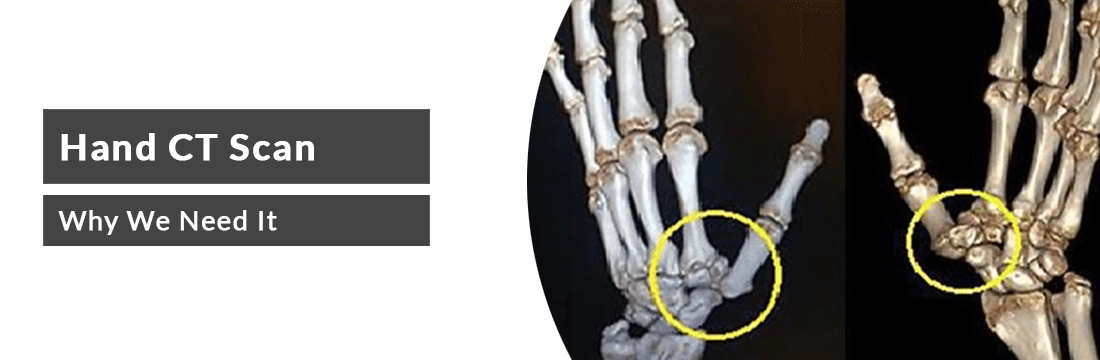

Hand is the terminal part of the vertebrate forelimb. Hand CT scan is the procedure which uses motorised X-rays with the computer tomography for the purpose of scanning the hand bones and joints. The scan also checks for the abnormalities in the hand and associated tissues and muscles. Hand possesses five fingers and the various joints connecting the fingers and finger joints. These joints make the hand a complex structure of bones and bone joints. CT gives the detailed view of this structure, healthcare experts can suggest the contrast for the scan as per the need.

Why do we need a hand CT scan?

- To check for the bony structure and morphology of the hand.

- To check for arthritis in the hand joints.

- To check for distal radial fractures and ulnar fractures.

- To check for scaphoid fractures or carpal fractures.

- To check for infection and inflammation.

- To check for soft tissue tumours.

- To check for hand disformations.

- To plan for the radiation or chemotherapy.

- To guide for hand surgeries.